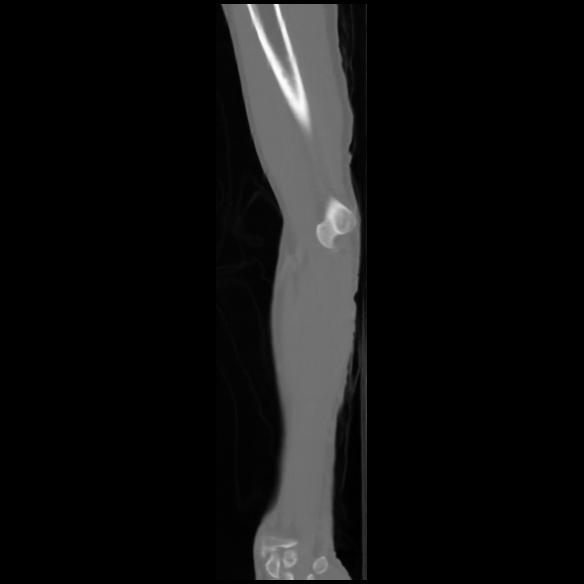

7 CUERPO,CE,Sagittal,3.000,CUERPO,Sagittal,